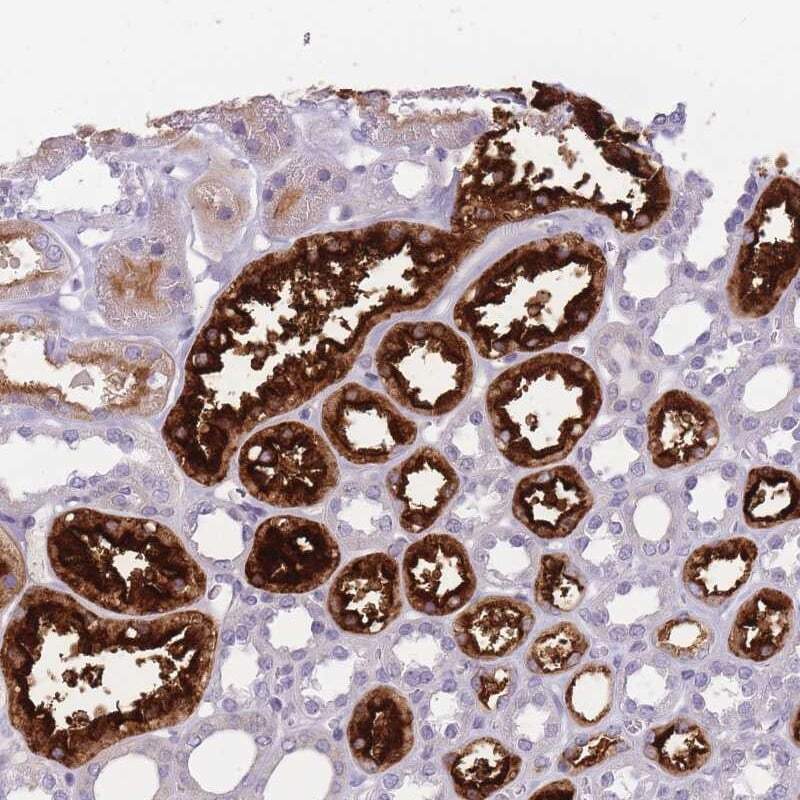

- Immunohistochemical analysis of GGT2 in human kidney using GGT2 Polyclonal Antibody (Product # PA5-61540) shows strong cytoplasmic and membranous positivity in tubular cells.